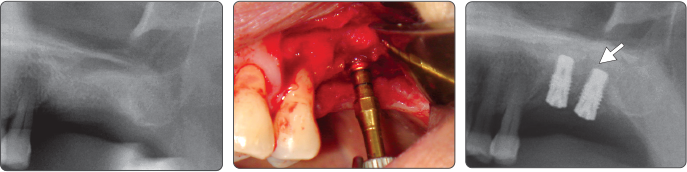

2. Синус-лифтинг (имплантат Ø5.0)

▶ Immediate Implantation and Sinus Lift Technique with Tap Drill (Ø5.0 Fixture)